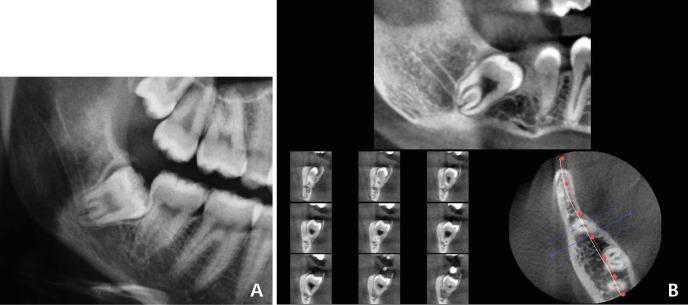

Preoperative radiographic assessment of the mandibular third molars is essential to prevent inferior alveolar nerve damage during extraction. The purpose of this study was to assess the reliability of panoramic signs of association between the roots of teeth and the canal, and to compare the panoramic signs with cone beam computed tomography (CBCT) findings.

CBCT images of 132 impacted mandibular third molars were evaluated to determine the association of the root to the canal. The CBCT findings were compared with the corresponding panoramic images. Logistic regression analysis was used to define the diagnostic criteria of the panoramic images.

AMONG THE PANORAMIC SIGNS, LOSS OF THE CORTICAL LINE WAS THE MOST FREQUENT RADIOGRAPHIC SIGN PREDICTING ASSOCIATION (SENSITIVITY: 79.31). Contact of the tooth with the canal was observed in all cases in which the loss of cortical line of the canal or darkening of the roots was found on the panoramic radiographs.

Darkening of the roots and loss of the cortical line on panoramic radiographs might be highly suggestive of the risk of nerve injury.

下颌第三磨牙术前的影像学评估对于防止拔牙过程中下牙槽神经损伤至关重要。本研究的目的是评估牙根与神经管之间关联的全景征象的可靠性,并将全景征象与锥形束计算机断层扫描(CBCT)结果进行比较。

对132颗下颌阻生第三磨牙的CBCT图像进行评估,以确定牙根与神经管的关联。将CBCT结果与相应的全景图像进行比较。采用逻辑回归分析来确定全景图像的诊断标准。

在全景征象中,皮质线消失是预测关联最常见的影像学征象(敏感性:79.31)。在全景片上发现神经管皮质线消失或牙根变黑的所有病例中,均观察到牙齿与神经管接触。

全景片上牙根变黑和皮质线消失可能高度提示神经损伤风险。